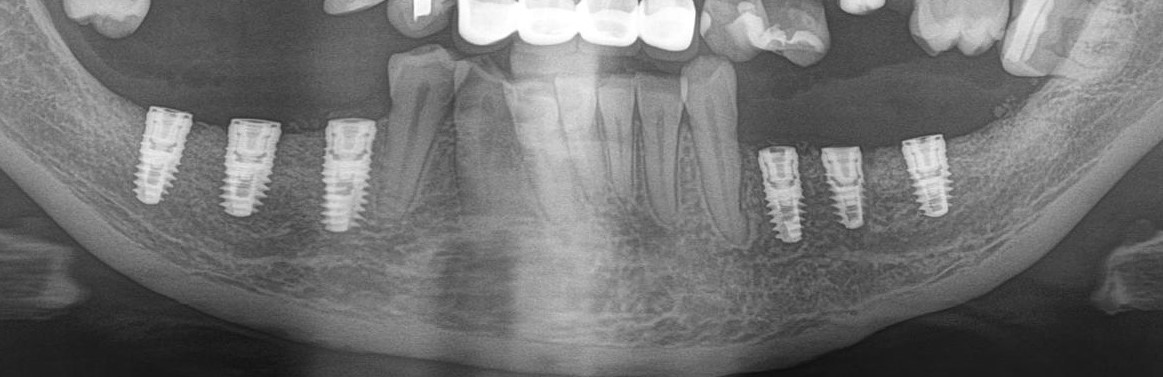

Рентгеновский снимок после операции (расщепление было проведено с двух сторон):

Снимок, сделанный через 5 месяцев после операции:

Обратите внимание, как изменился цвет кости. Она полностью восстановилась. На снимке этот участок стал белее.

Рентгеновский снимок после имплантации:

И спустя 3.5 месяца на этапе временных коронок (коронок не видно потому, что материал, из которого они изготавливаются, не рентгеноконтрастен):

Пиздюк в лице горизонтального зуба мудрости (на снимке справа) успешно был удалён.